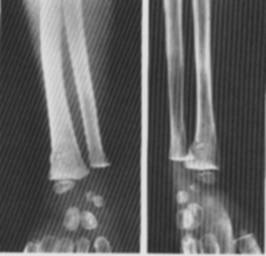

Fig. 112 -    Fractura in lemn verde

Fig.    113 - Fractura subperiostala

■fractura in lemn verde in care indoirea traumatica a osului duce prin flectare, la o linie de fractura incompleta sau denivelare corticala marginala la nivelul convexitatii;